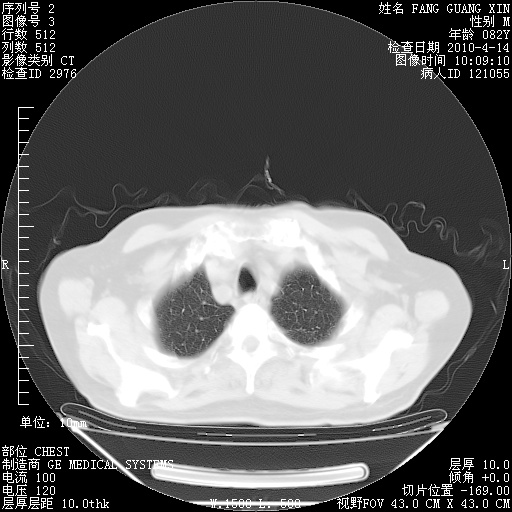

4月14日肺部CT

楼主| 发表于 2010-4-28 16:51 | 显示全部楼层

楼主| 发表于 2010-4-28 16:53 | 显示全部楼层

肺部CT平扫未见异常。